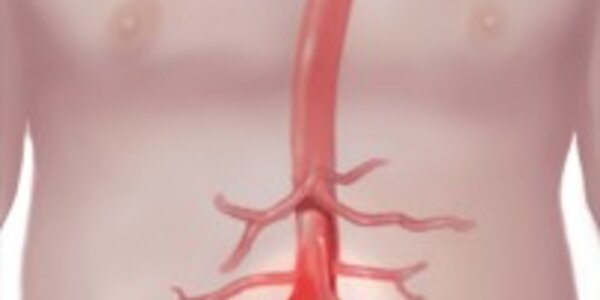

Abdominal Aortic Aneurysms: Who Needs Screening And Treatment

An abdominal aortic aneurysm is a potentially life-threatening condition: If the body's major blood vessel ruptures, it can prove deadly. Abdominal aortic aneurysms are a bulge in the aorta, which is the body's largest artery and is located in the abdomen above the belly button. The greatest risk is that the aneurysm will rupture. That's scary but who should be watched? The U.S. Preventive Services Task Force recently updated its recommendations on screening and Mayo Clinic vascular surgeon Peter Gloviczki, M.D., outlines how people are diagnosed and how surgery, which now includes a…